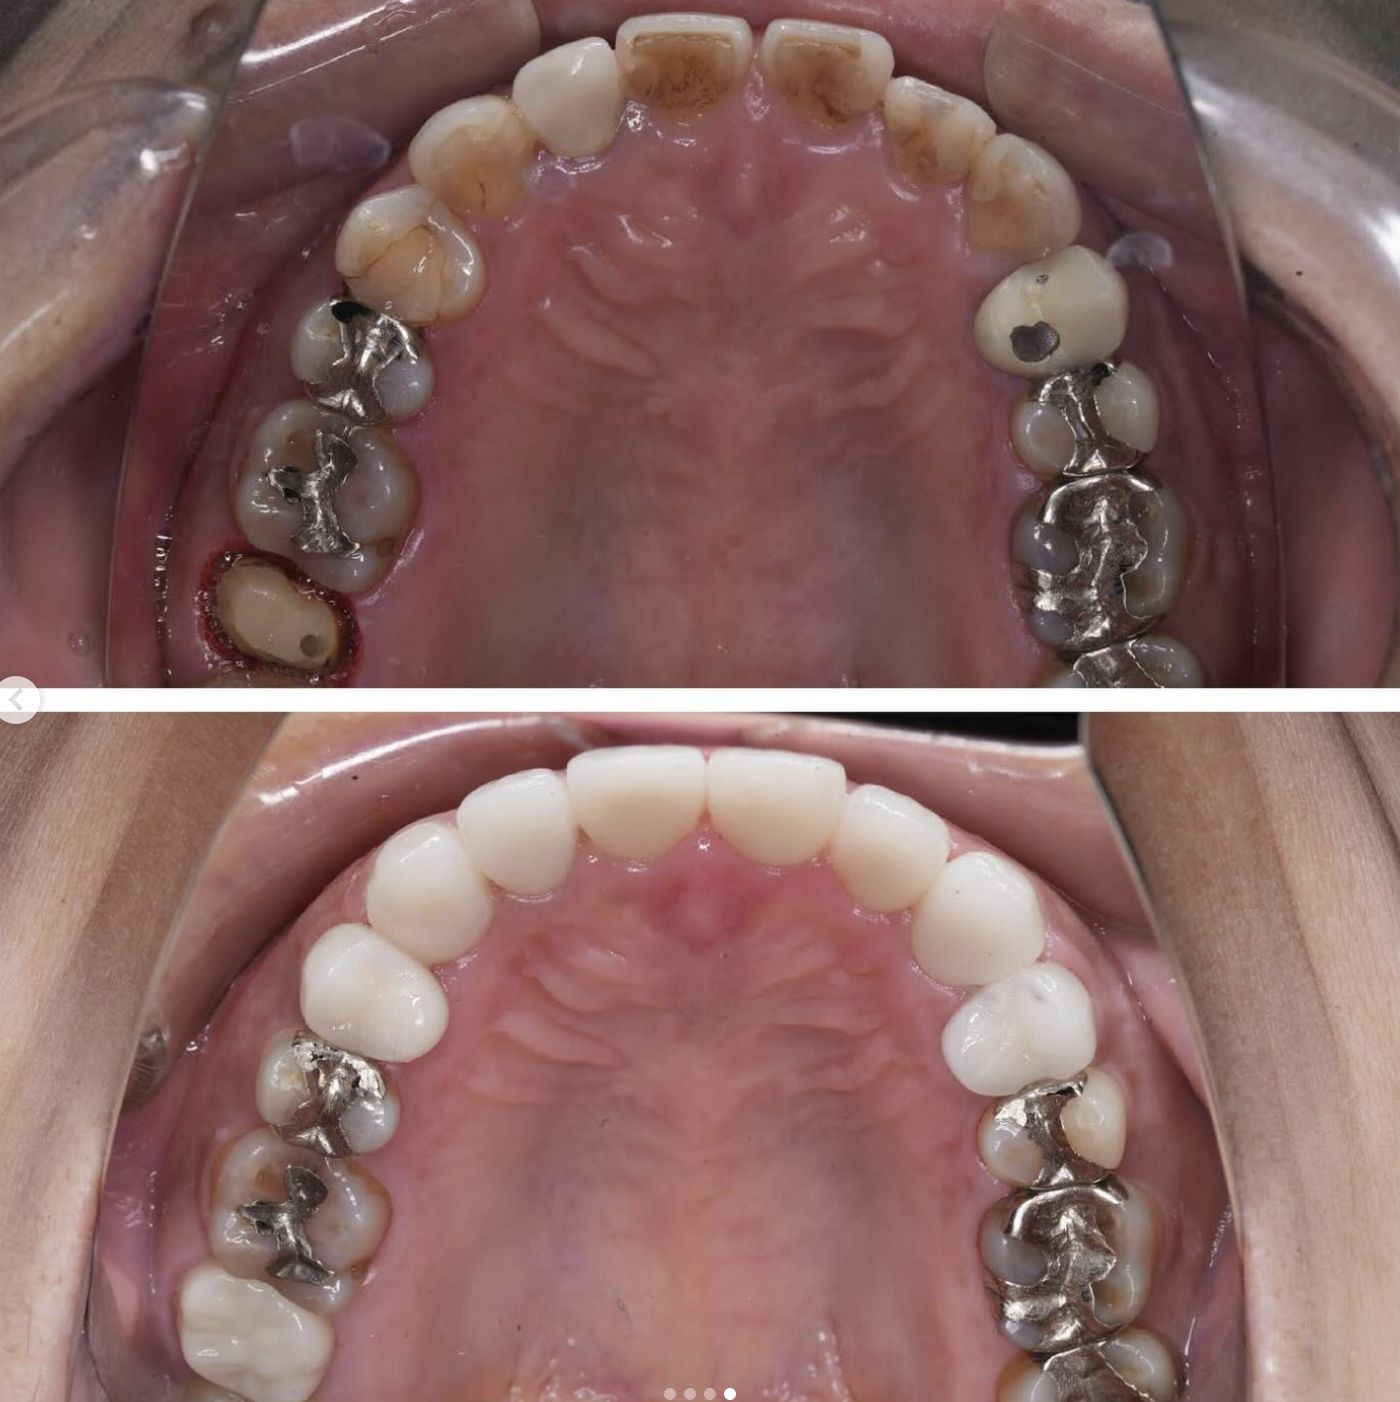

Case012 – インプラント

前歯の審美歯科から、奥歯の虫歯診療、歯がないところのインプラント治療まで口腔内を全体的に当院で治療させて頂いた患者様です。

外見もとても綺麗になり、奥歯でも物を噛めるようになってとても喜んで頂けました。

担当 理事長 佐藤悠野